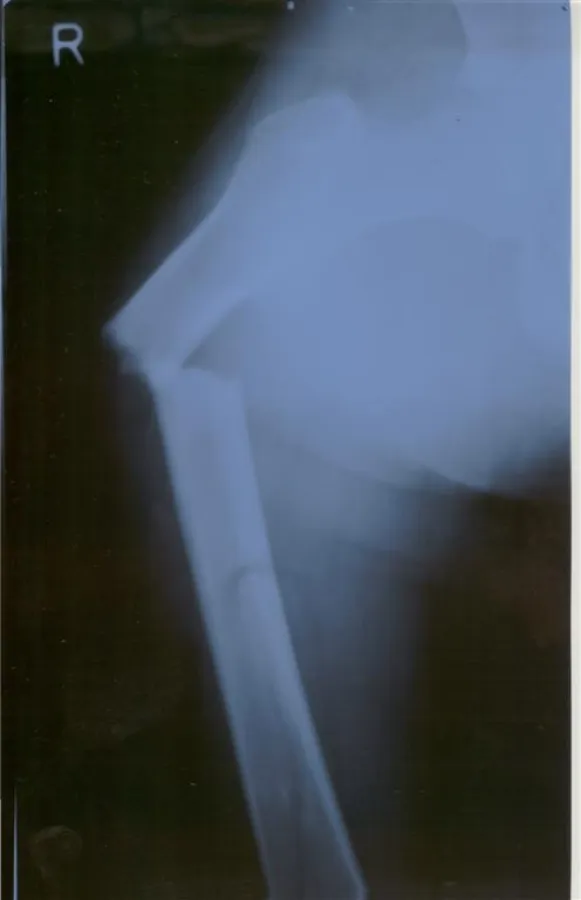

Die HPP gehört zu den seltenen Knochenstoffwechselstörungen und wird daher oft nicht oder erst spät korrekt diagnostiziert. Gerade auch, weil die Krankheit bei den erwachsenen Patienten oft erst im mittleren Lebensalter mit Ermüdungsbrüchen in Erscheinung tritt und daher leicht mit der klassischen Osteoporose verwechselt werden kann.

Im Gegensatz zur Osteoporose weisen bei der Hypophosphatasie die Patienten normale, z.T. sogar gefährlich erhöhte Kalzium- und Phosphat-Werte auf. Dementsprechend sind auch alle Behandlungsmethoden für die Osteoporose bei der Hypophosphatasie völlig ungeeignet. Hochdosiertes Kalzium und Vitamin D können den HPP-Patienten sogar weitere Schäden zufügen (Nierensteine, Knochenentzündungen).